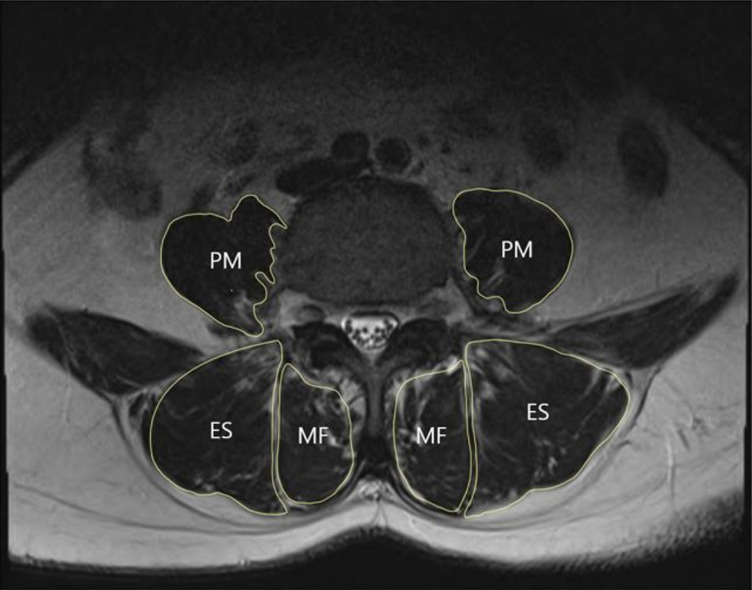

Methods: This retrospective study included a total of 146 subjects who underwent Fishermen's health survey conducted between June 2018 and August 2020. LBP was evaluated through visual analogue scale (VAS) and Oswestry Disability Index (ODI). Sagittal spino-pelvic parameters were measured from whole spine standing X-rays. Back muscle cross-sectional areas were identified through lumbar spine magnetic resonance imaging and body composition was analyzed through bioelectrical impedance analysis.

Results: The study included 75 males and 71 females, with an average age of 58.33 years for males and 56.45 years for females. Female subjects exhibited higher VAS and ODI scores, larger pelvic tilt (PT) and trunk fat mass and smaller trunk muscle mass compared to males. In female, ODI positively correlated with sagittal vertical axis (SVA) and PT. No significant correlations were found between ODI scores and body composition in either sex. The high ODI group showed greater SVA, PT, and pelvic incidence-lumbar lordosis and higher trunk fat/muscle ratio. Psoas muscle mass, total and skeletal muscle mass and trunk muscle mass of that group were smaller than those of low ODI group.